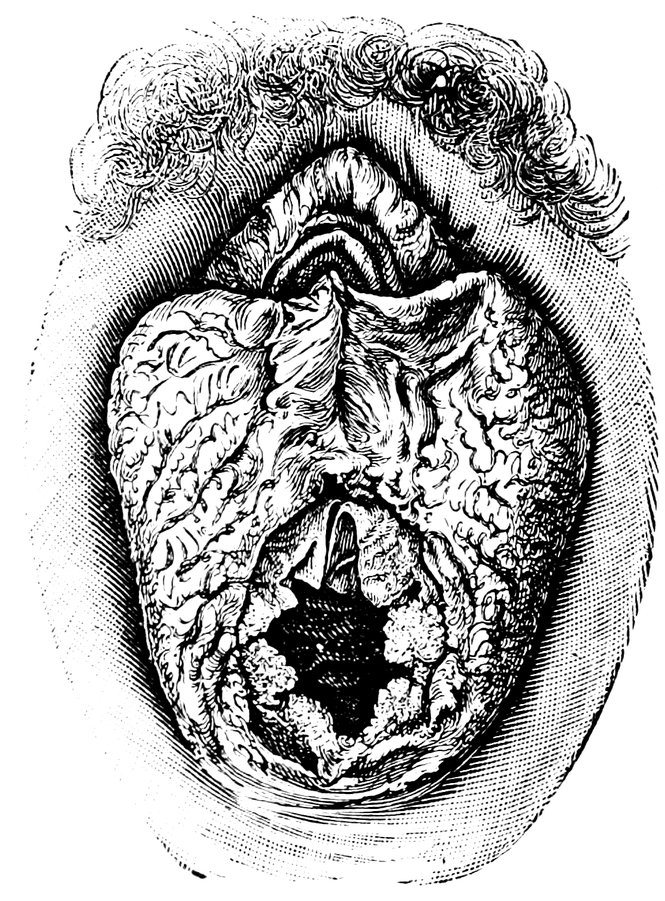

| 44. | Carunculæ Myrtiformes in a Primipara | 71 |

| 45. | Vaginal Inlet of a Multipara, without Carunculæ Myrtiformes. Slight Prolapse of Anterior and Posterior Vaginal Walls | 71 |

| 48. | The female pudendum, or vulva, with the labia majora | 204 |

| 49. | Vestibule of the vagina, with the labia minora or nymphæ, etc | 205 |